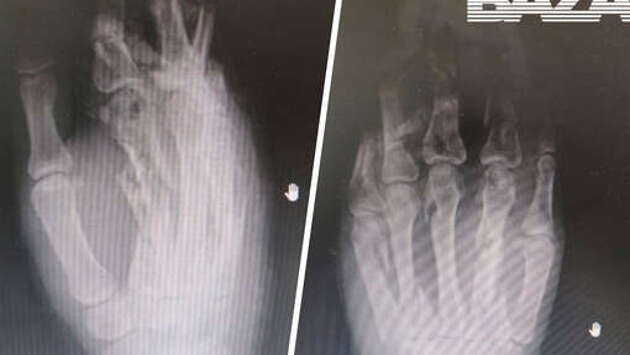

В Подмосковье врачи спасли кисть девушке, рука которой застряла в электрической мясорубке: почти все ее пальцы сломаны и частично перемолоты, сообщается в Telegram-канале "Baza". По неизвестной причине кисть 26-летней девушки застряла в электрической мясорубке во время работы прибора. В шоковом состоянии потерпевшая была доставлена в местную больницу. Врачи осмотрели пациентку и провели необходимые процедуры, оказалось, что почти все пальцы ее левой руки сломаны и частично перемолоты. Травматологи и анестезиологи три часа проводили необходимые медицинские вмешательства, в результате которых удалось спасти не только кисть девушки, но и все ее пальцы. Сейчас поврежденная конечность полностью обработана. Для ее восстановления врачи установили на руке специальный аппарат, который поможет облегчить этот процесс. Ранее в Томске врачи пришили годовалому мальчику пальцы, которые были отрезаны мясорубкой.